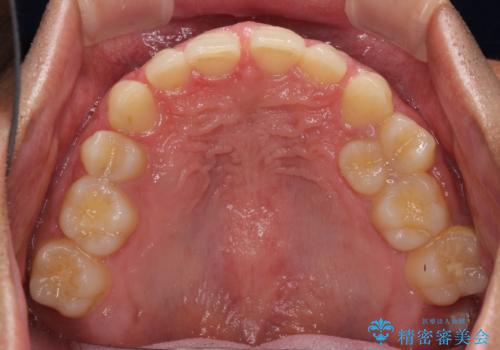

著しいディープバイトと隙間だらけの歯列

- 歯のデコボコと歯の隙間を気にして来院された患者様です。

隙間の原因は、埋伏や前後に重なってしまっている上顎小臼歯と、下の前歯が見えなくなるくらいのディープバイトで、それらを改善する必要がありました。

アンカースクリューを用いて下に位置している上顎前歯を持ち上げるとともに、ワイヤー装置によりディープバイトの原因である奥歯の傾斜を改善することで、矯正治療を行っていくこととしました。

また、矯正治療に際し、4本全ての親知らずと、埋もれている右上小臼歯を事前に抜去することとしました。